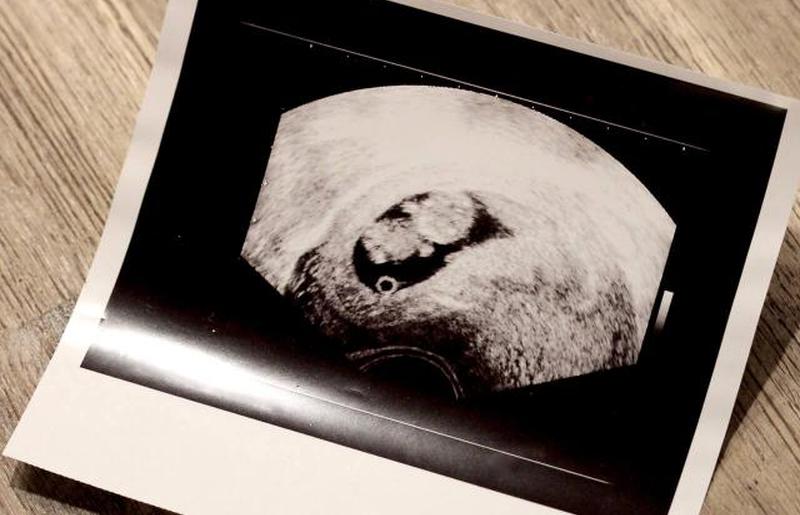

Если вы не проходили УЗИ в семь недель, это может быть первый раз, когда вы видите своего растущего ребенка или детей. Во время вашего восьминедельного визита ваше УЗИ подтвердит, сколько плодов присутствует, а также размер, гестационный возраст и общее состояние здоровья вашего ребенка.

На восьмой неделе беременности ваш ребенок все еще похож на маленькую каплю, но начинает больше походить на человеческого ребенка. В то время как врачи используют 8-недельное УЗИ, чтобы многое рассказать о вашей беременности, на самом деле вы не можете увидеть очень многого.

На экране УЗИ вы увидите маленький плод в форме арахиса. Если у вас уже были предыдущие УЗИ, то это будет больше похоже на ребенка, чем ваше предыдущее, так как маленькие ручки и ножки становятся более заметными. Имейте в виду, однако, что ваш плод чуть меньше дюйма в длину . Возможно, вы не сможете легко разглядеть черты лица, потому что он такой крошечный.

Во время УЗИ ваш врач или техник УЗИ нанесет вам на живот гель и с помощью палочки определит местонахождение ребенка. Ваш врач может также назначить вам трансвагинальное УЗИ. Поскольку ребенок очень мал, трансвагинальное УЗИ даст вам лучшее представление о вашем самородке, а также о ваших репродуктивных органах. Вы увидите свою матку, растущего ребенка и пуповину.